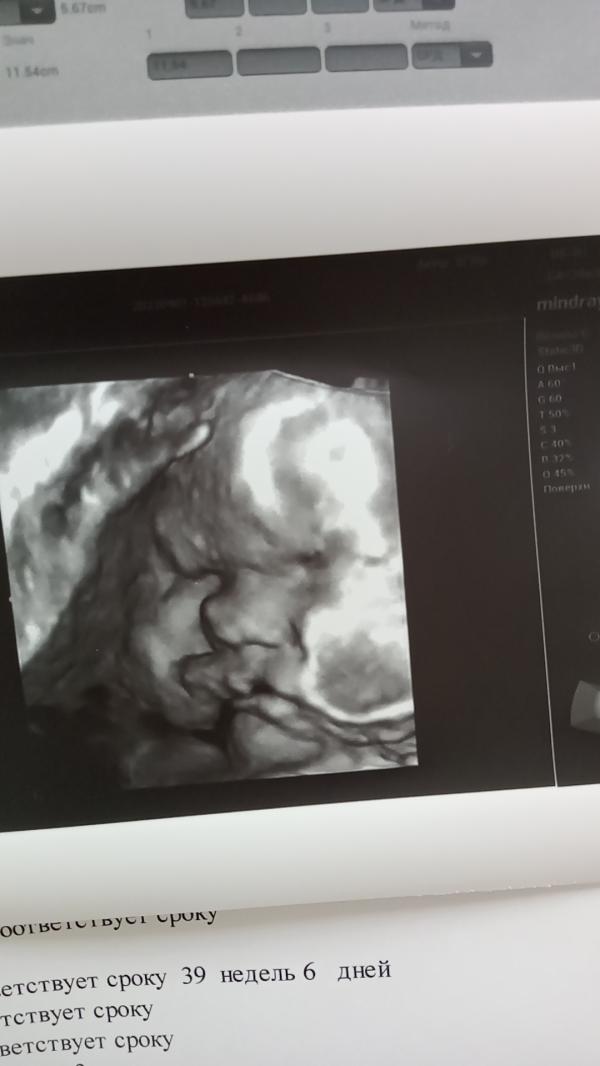

Сходили мы на УЗИ, всё хорошо 🙏🙏🙏🙏,так что могу ходить спокойно. Примерный вес 3800. Сколько у вас весили малышки в 39 недель и каким весом родились